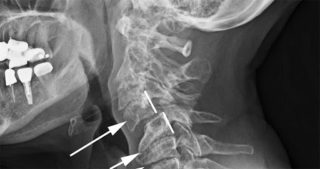

Смещение рядом стоящих позвоночных тел относительно друг друга в медицине именуют спондилолистезом. В большинстве случаев диагностируют нарушение анатомического расположения 4 и 5 шейного позвонка.

Если есть подозрение на смещение атланта (первого шейного позвонка), проводится рентген через ротовую полость.

По результатам диагностики можно подтвердить факт смещения тел позвоночника и определить его степень:

- первая: позвонок на 25% отклонен от своего места локализации;

- вторая: тело смещено на 50%;

- третья: позвонок отклоняется на 75%;

- четвертая: тело смещено более чем на 75%.